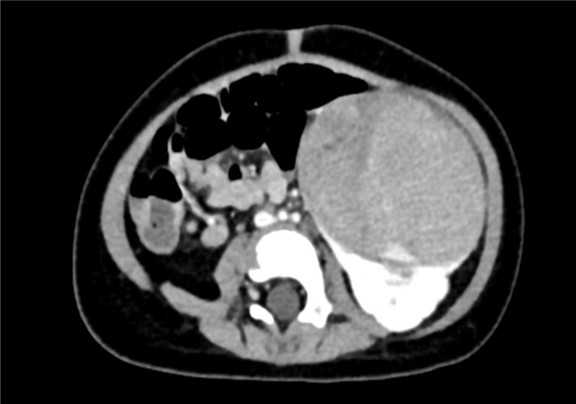

上腹部增强CT:左肾巨大占位性病变,疑似肾母细胞瘤

术前CT检查:

动脉期

静脉期

平衡期